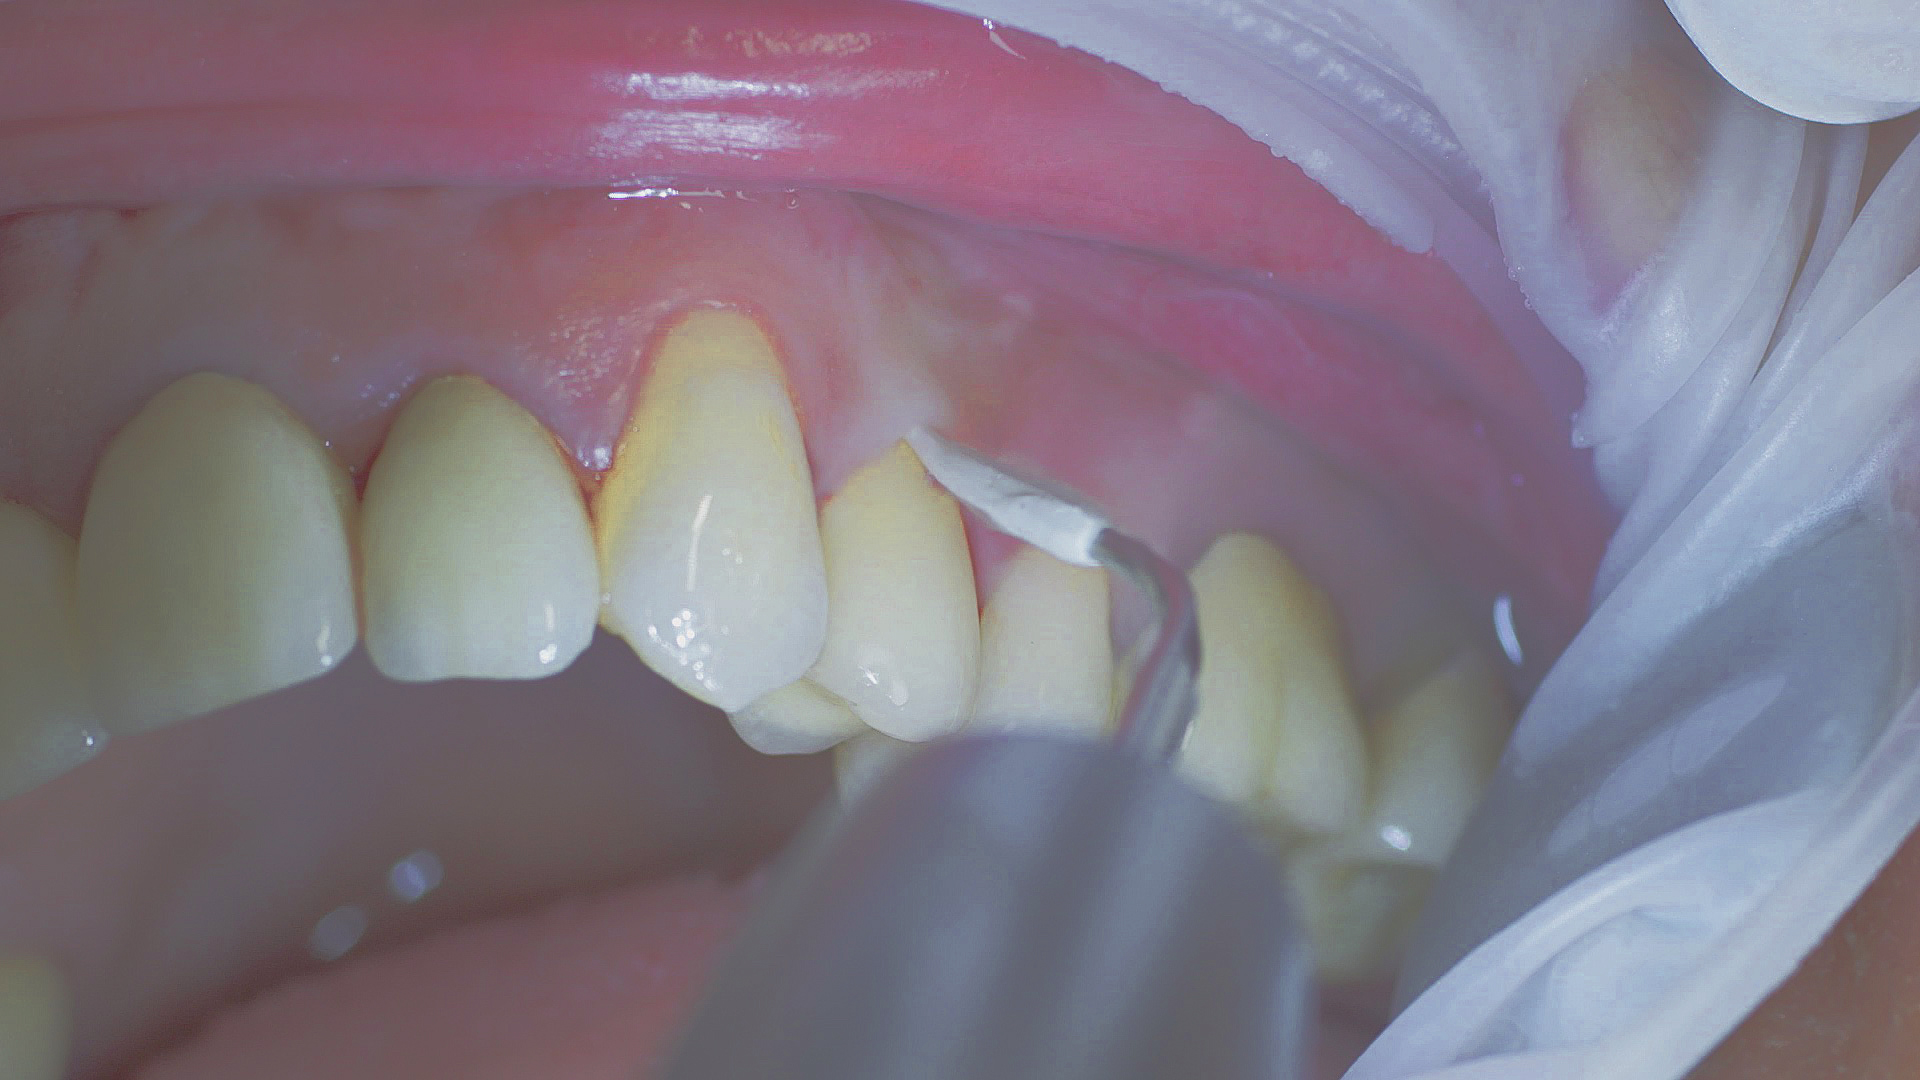

Un traitement parodontal essentiellement inchangé

Tous les examens dentaires reposent sur l’étude des antécédents médicaux détaillés, associée à un diagnostic ciblé contenant le plus de détails possible. Le chirurgien-dentiste enregistre les facteurs de risque systémiques tels que le diabète ou le tabagisme et identifie toute augmentation de la tendance potentielle à l'inflammation.[3] Les tissus durs et mous sont examinés et les poches parodontales sont sondées dans le cadre d’un test de dépistage selon le PSR (Periodontal Screening and Recording). En cas de résultats anormaux, l’état du parodonte est ensuite enregistré et un traitement est démarré si nécessaire. Ce traitement débute par la gestion professionnelle du biofilm à l'aide par exemple de cupules rotatives et de composés de polissage (Fig. 1) et comporte des instructions complètes sur l’hygiène buccodentaire. Les systèmes à ultrasons restent une alternative ou un complément efficace aux instruments manuels pour le détartrage subgingival et la gestion du biofilm (présentation du Pr Dr Ulrich Schlagenhauf ;

Une bonne hygiène buccodentaire personnelle et une gestion professionnelle du biofilm, par exemple à l'aide de cupules et de brossettes, sont favorables à la santé parodontale et péri-implantaire.

Fig. 1 : Une bonne hygiène buccodentaire personnelle et une gestion professionnelle du biofilm, par exemple à l'aide de cupules et de brossettes, sont favorables à la santé parodontale et péri-implantaire.